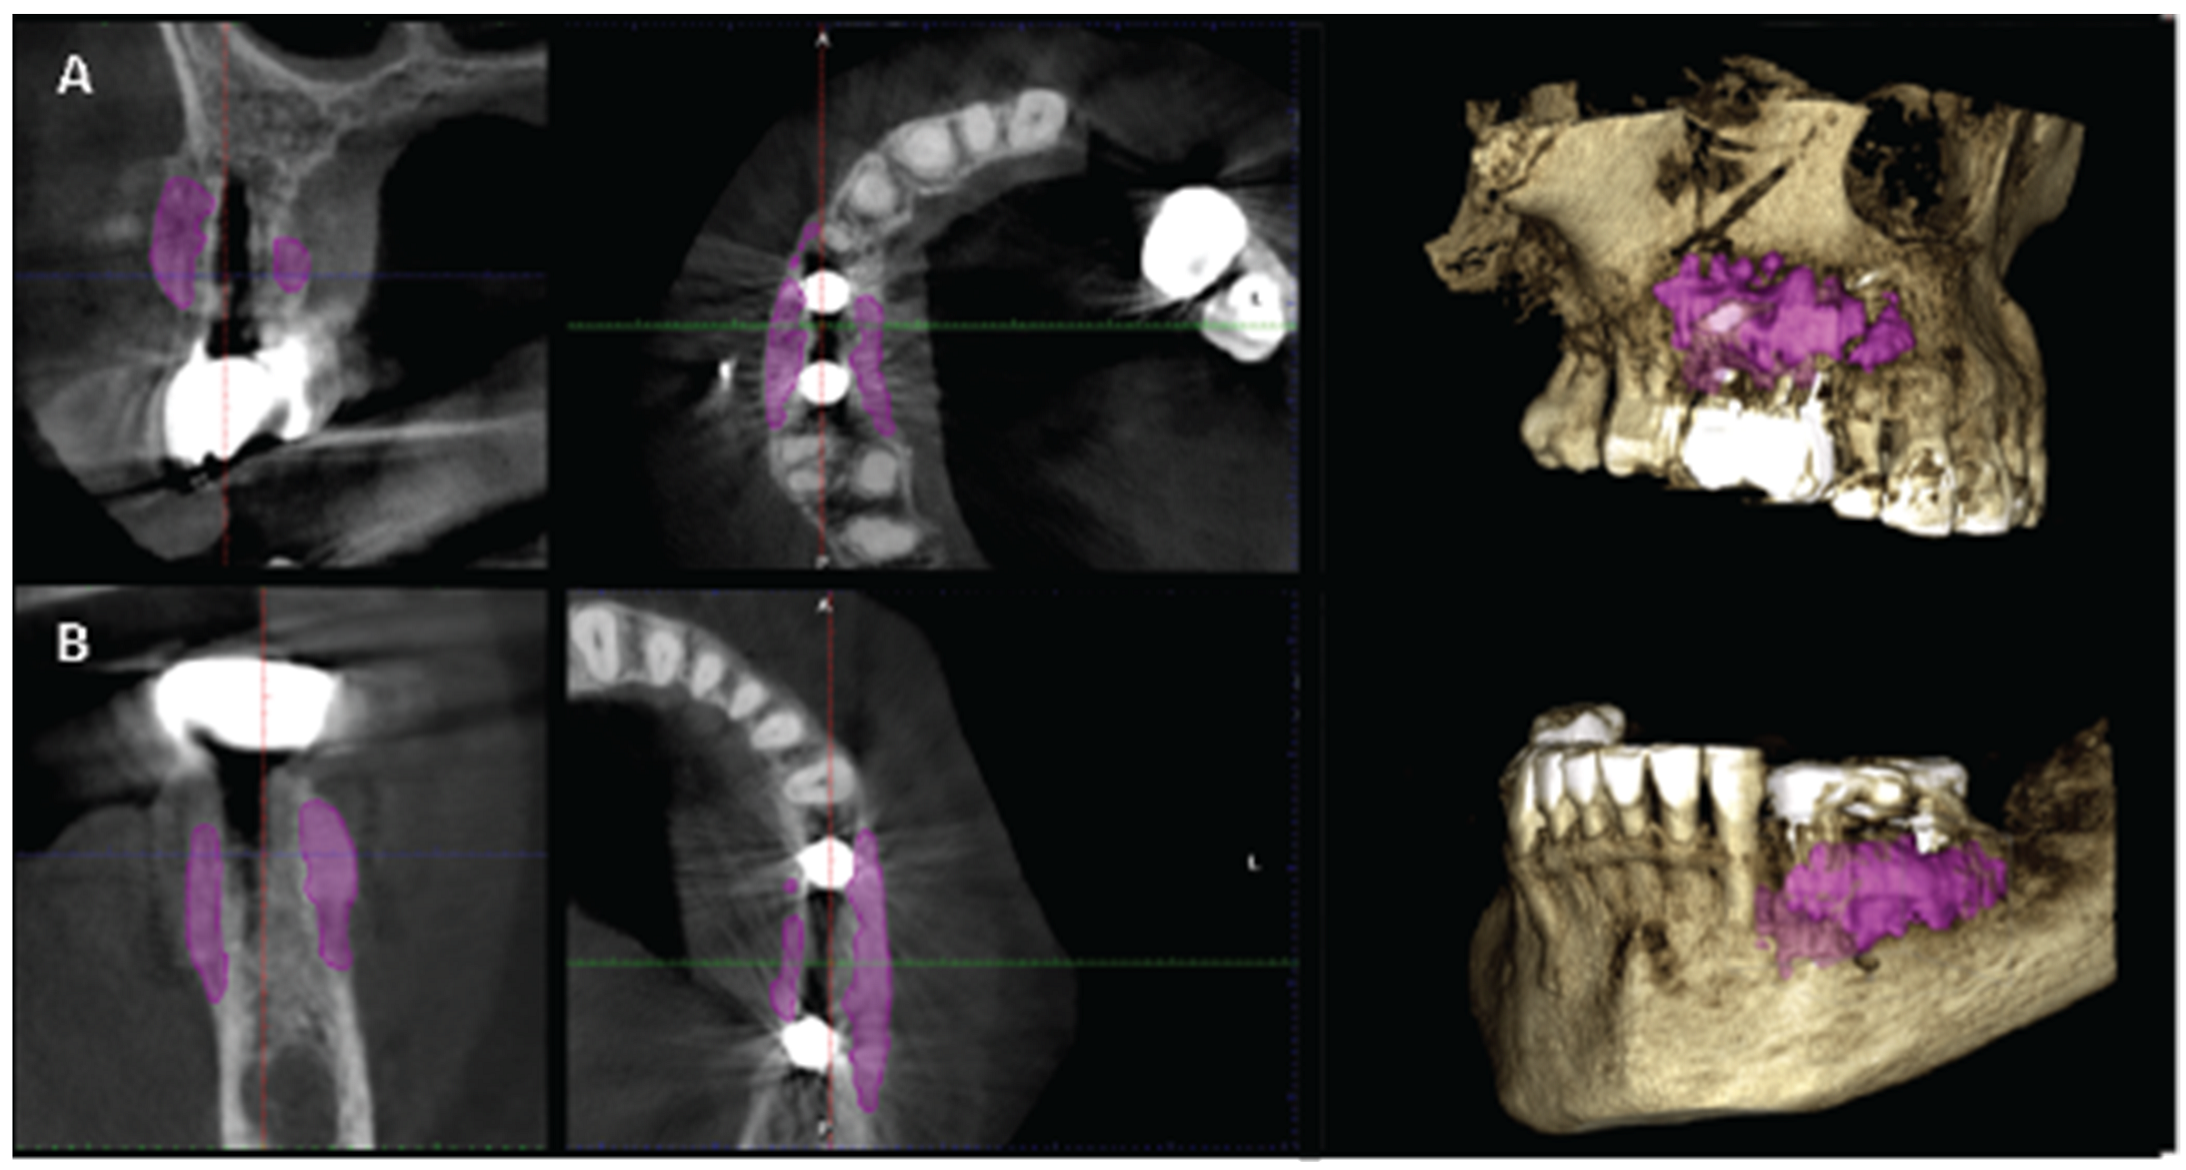

2.4. Case 2

2.5. Stage 1

3. Results

Soft Tissue Configuration Results: